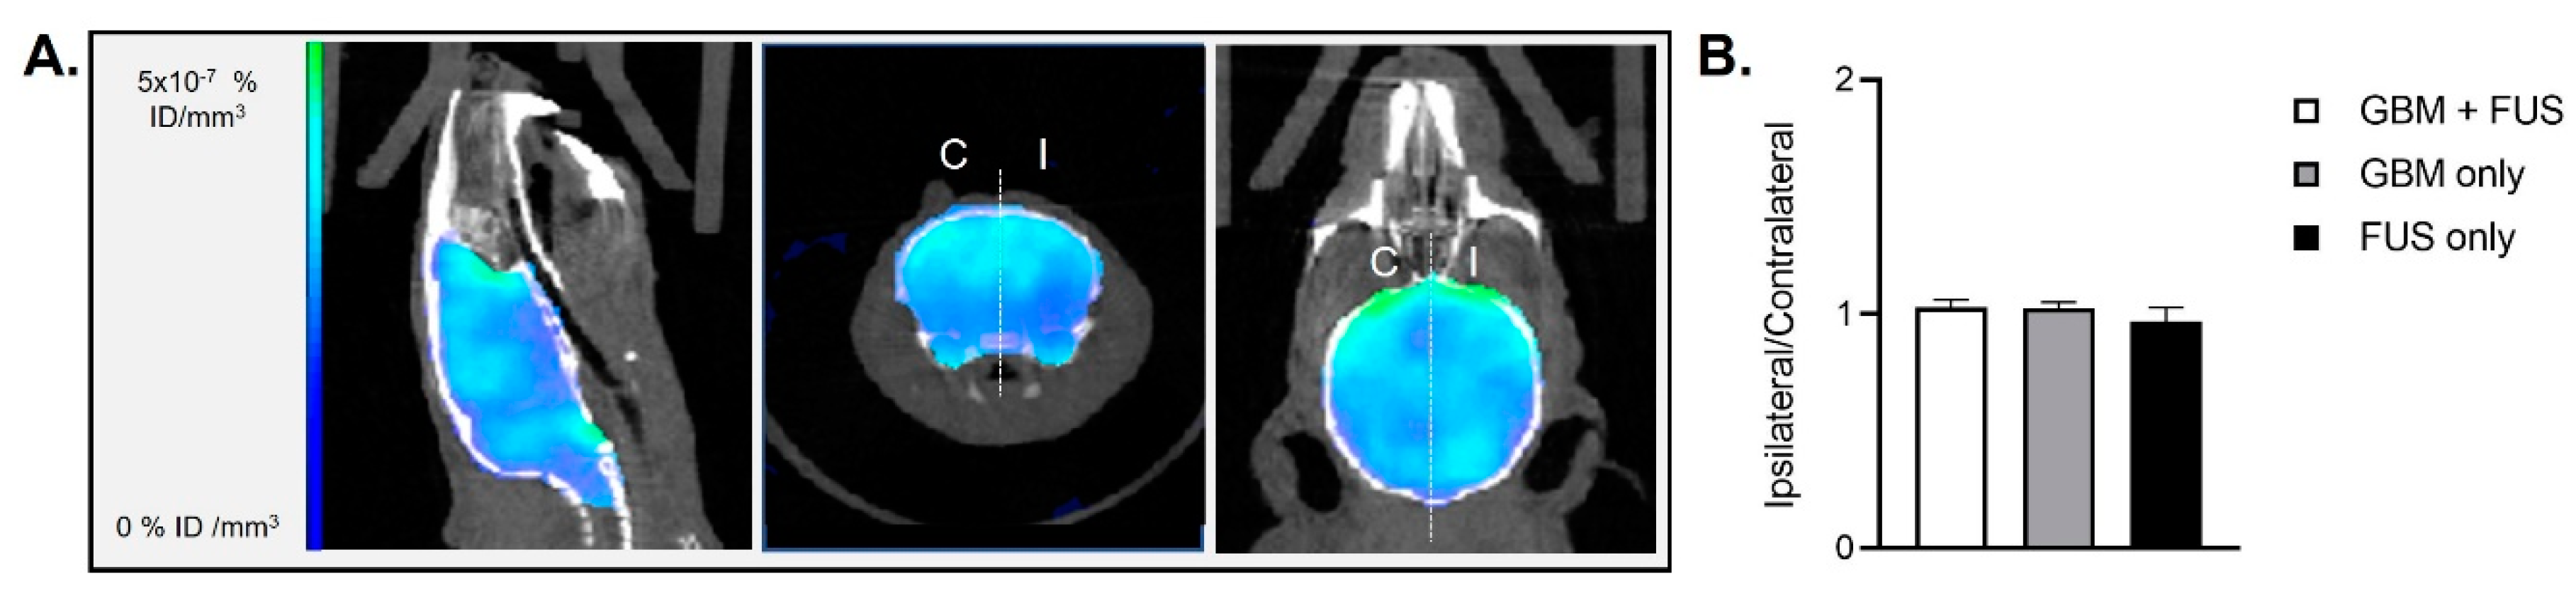

- Hugon, G.; Goutal, S.; Dauba, A.; Breuil, L.; Larrat, B.; Winkeler, A.; Novell, A.; Tournier, N. [(18)F]2-Fluoro-2-deoxy-sorbitol PET Imaging for Quantitative Monitoring of Enhanced Blood-Brain Barrier Permeability Induced by Focused Ultrasound. Pharmaceutics 2021, 13, 1752. [Google Scholar] [CrossRef]